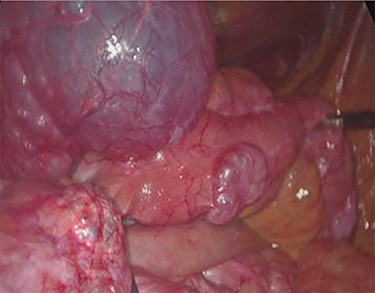

Unfortunately, once he returned home his temperature started to rise up to 38°C and he was readmitted to the hospital. A new contrast-enhanced Chest/Abdomen CT showed a bilateral pneumonia and a massive amount of intraperitoneal free gas, mainly in the abdominal upper quadrants (Fig. 2). No fat stranding, nondilated bowel, no vascular abnormalities and no free fluid were detected. Although the CT showed an evident worsening, the patient still remained completely asymptomatic on physical examination. Accordingly, he started to be treated with meropenem for pneumonia (Escherichia coli was isolated into the sputum) and he finally agreed to underwent diagnostic laparoscopy. Surprisingly, that was definitely not a case of pneumoperitoneum but an idiopathic PCI as we found multiple intramural air content cyst, about 2–3 cm in diameter, all around the small bowel loops and mesentery (Fig. 3). No intra-abdominal maneuvers were made. The patient had an unremarkable recovery (Clavien–Dindo classification grade was 1) [3] and he was discharged home on postoperative Day 15 in well condition, once he had recovered from pneumonia.

Intra-operatory findings of pneumatosis cystoides intestinalis of the small bowel.